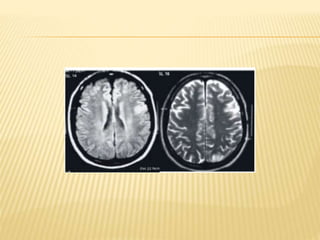

HALLAZGOS NEURORRADIOLOGICOS

 COMBINACION DE ZARANDEO

VIOLENTO, IMPACTO DE ALTA FUERZAE

HIPOXIA-ISQUEMIA.

 ESTAN PRESENTES DENTRO DE LAS

PRIMERAS HORAS DEL ASALTO.

 SIGNO: PERDIDA DE DIFERENCIACION

ENTRE LAS SUSTANCIAS GRIS Y

BLANCACEREBRAL EN LAS REGIONES

CORTICAL SUBCORTICAL, EN LOS

GANGLIOS BASALES PROFUNDOS Y LAS

REGIONES CAPSULARES, O EN AMBOS.

HALLAZGOS NEURORRADIOLOGICOS COMBINACION DE ZARANDEO VIOLENTO, IMPACTO DE ALTA FUERZAE HIPOXIA-ISQUEMIA.  ESTAN PRESENTES DENTRO DE LAS PRIMERAS HORAS DEL ASALTO.  SIGNO: PERDIDA DE DIFERENCIACION ENTRE LAS SUSTANCIAS GRIS Y BLANCACEREBRAL EN LAS REGIONES CORTICAL SUBCORTICAL, EN LOS GANGLIOS BASALES PROFUNDOS Y LAS REGIONES CAPSULARES, O EN AMBOS.